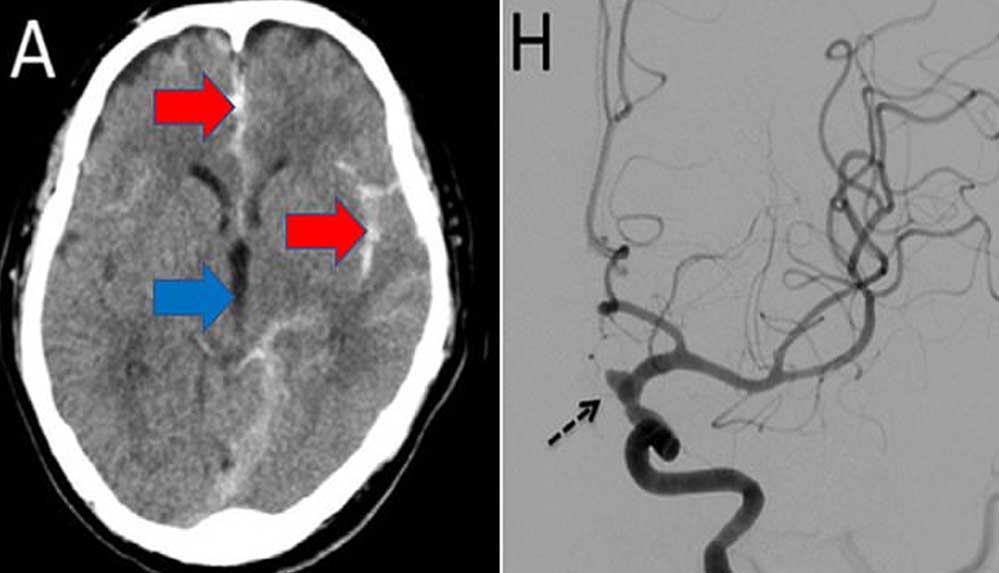

Vakaya ait tomografi görüntülerinde hastanın beyinde kanamalar oluştuğu görüldü.